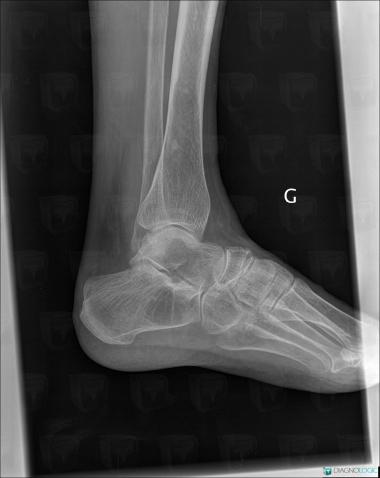

Avascular necrosis, Talus, Calcaneus, X rays

Here is the specific information in the key image above:

- Diagnosis Avascular necrosis, Location(s) Calcaneus, with gamuts Lucent lesion in footTalus, with gamuts Lucent lesion in foot